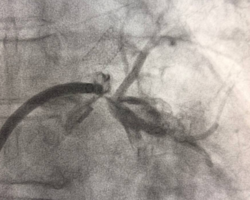

Вмешательство проводилось через бедренный венозный доступ под местной анестезией. Основная сложность операции заключалась в полной окклюзии обеих легочных вен и необходимости точной навигации инструментов в условиях ограниченной визуализации. После реканализации поражённых участков были имплантированы стенты, обеспечившие надёжное восстановление просвета сосудов и полноценный венозный отток из лёгких.

В результате кровоток по левой верхней и левой нижней легочным венам полностью восстановлен. Состояние пациента стабилизировалось, одышка регрессировала. В настоящее время пациент чувствует себя хорошо.